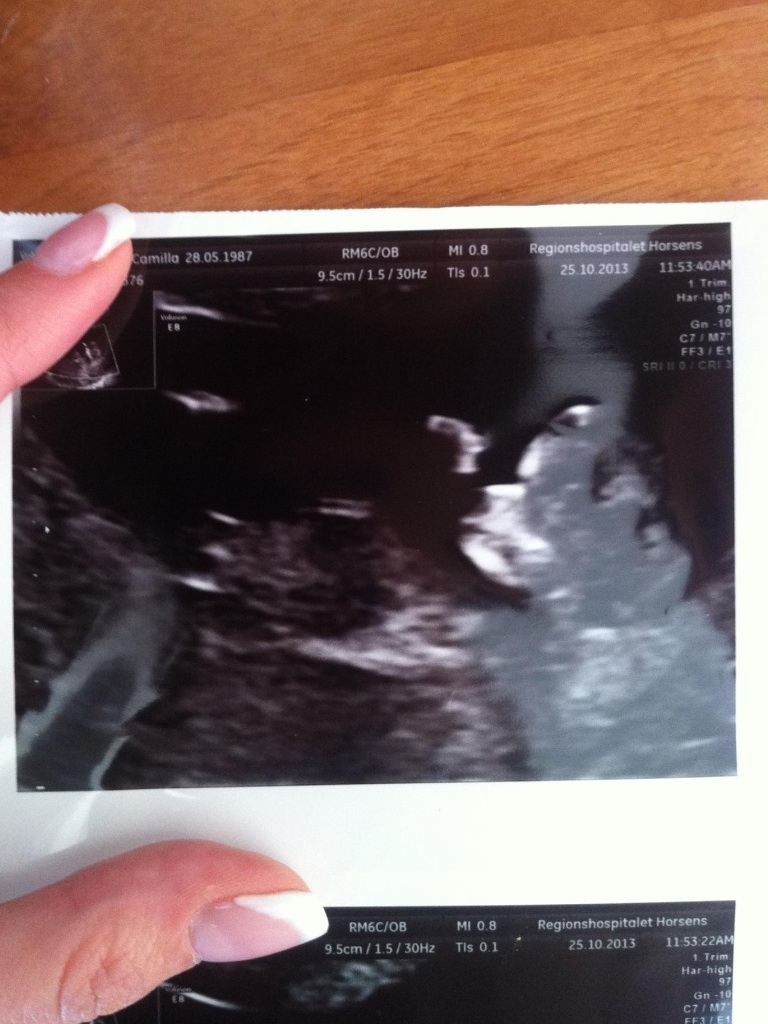

12 weeks ultrasound..!Attachment 14983